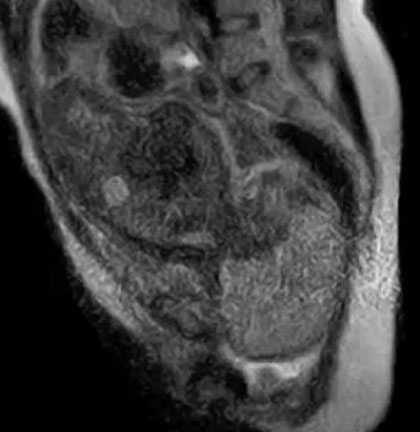

(VTC News) - Các bác sĩ tại một bệnh viện ở Berlin (Đức) đã đưa ra một đoạn video cho thấy những hình ảnh đầy sống động trong hành trình đi ra khỏi bụng mẹ.